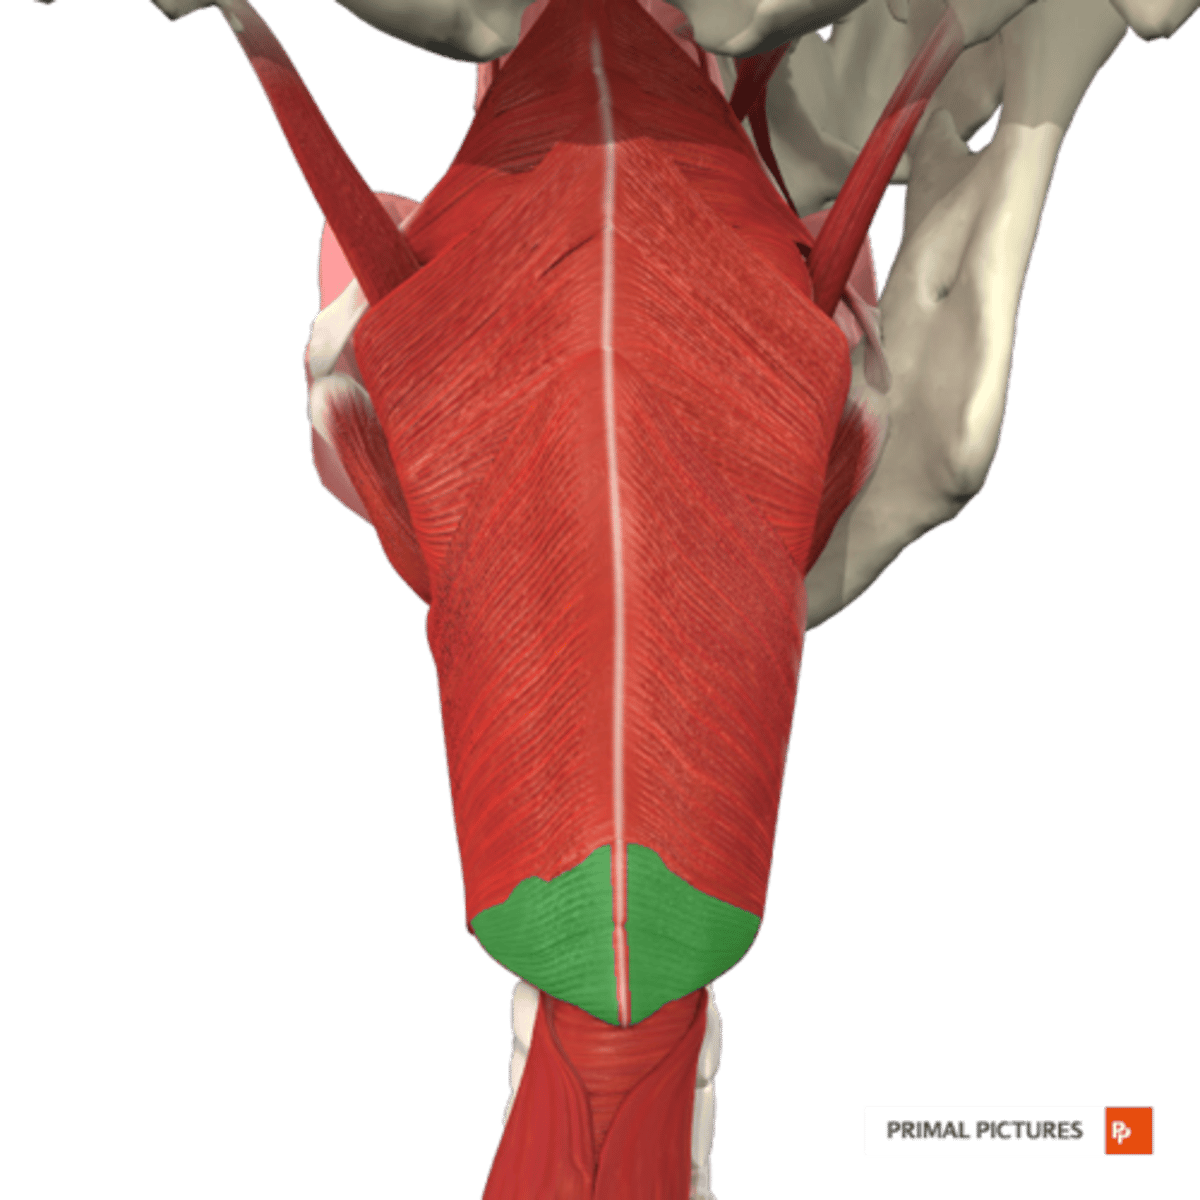

Constrictor Muscle Actions

Constrictor muscles all pull pharyngeal

walls inward and forward to constrict

the pharyngeal tube

Cricopharyngeus also assists in closing

the upper esophageal sphincter